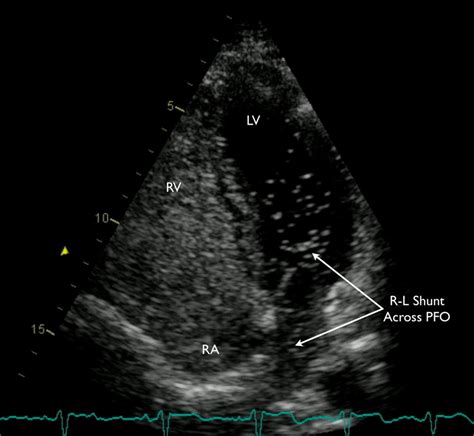

1819×1545

ahajournals.org

Atrial Fibrillation After Patent Foramen Ovale Closure: Incidence ...